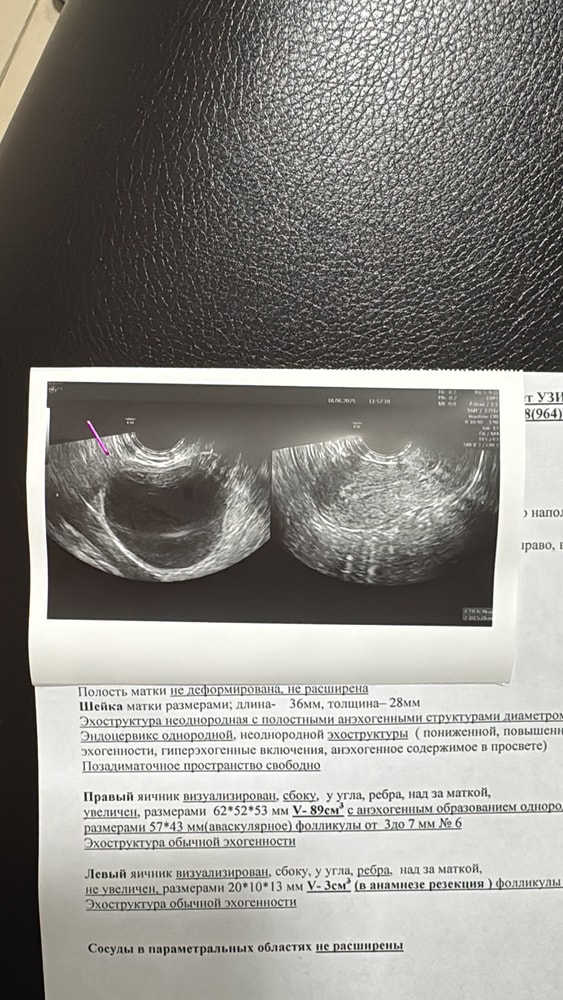

Почти два месяца назад была лапара по удалению эндометриодной кисты. В этом месяце планирую криоперенос. УЗИстка сказала , что с водянистой кистой не возьмут меня. У кого была такая ситуация? И почему написали в заключении «обеднение фолликулярного аппарата яичников»? Ведь в каждом яичнике от 3 до 7 фолликуллов